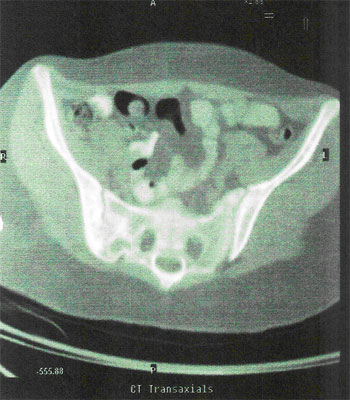

Prostate :

INITIAL STAGE

08-Aug-2006

USG AFTER HERBAL ONCOLOGY

22-Nov-2006